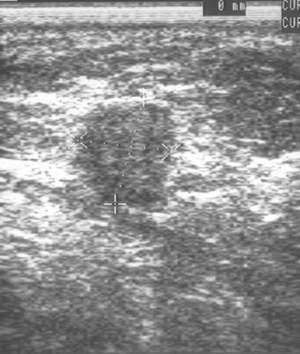

Mit den neuen hochauflösenden Geräten lassen sich auch kleine Befunde darstellen:

Diagnose: 11 mm großes Mamma-Carcinom